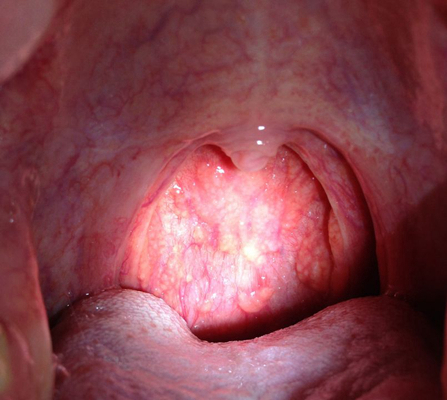

扁桃體結石

扁桃體結石

扁桃體結石

扁桃體結石

扁桃體結石

扁桃體結石

扁桃體結石

扁桃體結石

扁桃體結石

扁桃體結石

扁桃體結石

扁桃體結石

扁桃體結石

扁桃體結石

扁桃體結石

扁桃體結石

扁桃體結石

扁桃體結石

扁桃體結石

扁桃體結石